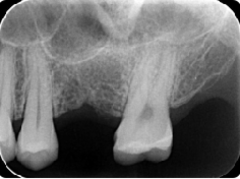

歯周病が進行し、グラグラして物が嚙めず、抜歯してインプラントにしていくことに。